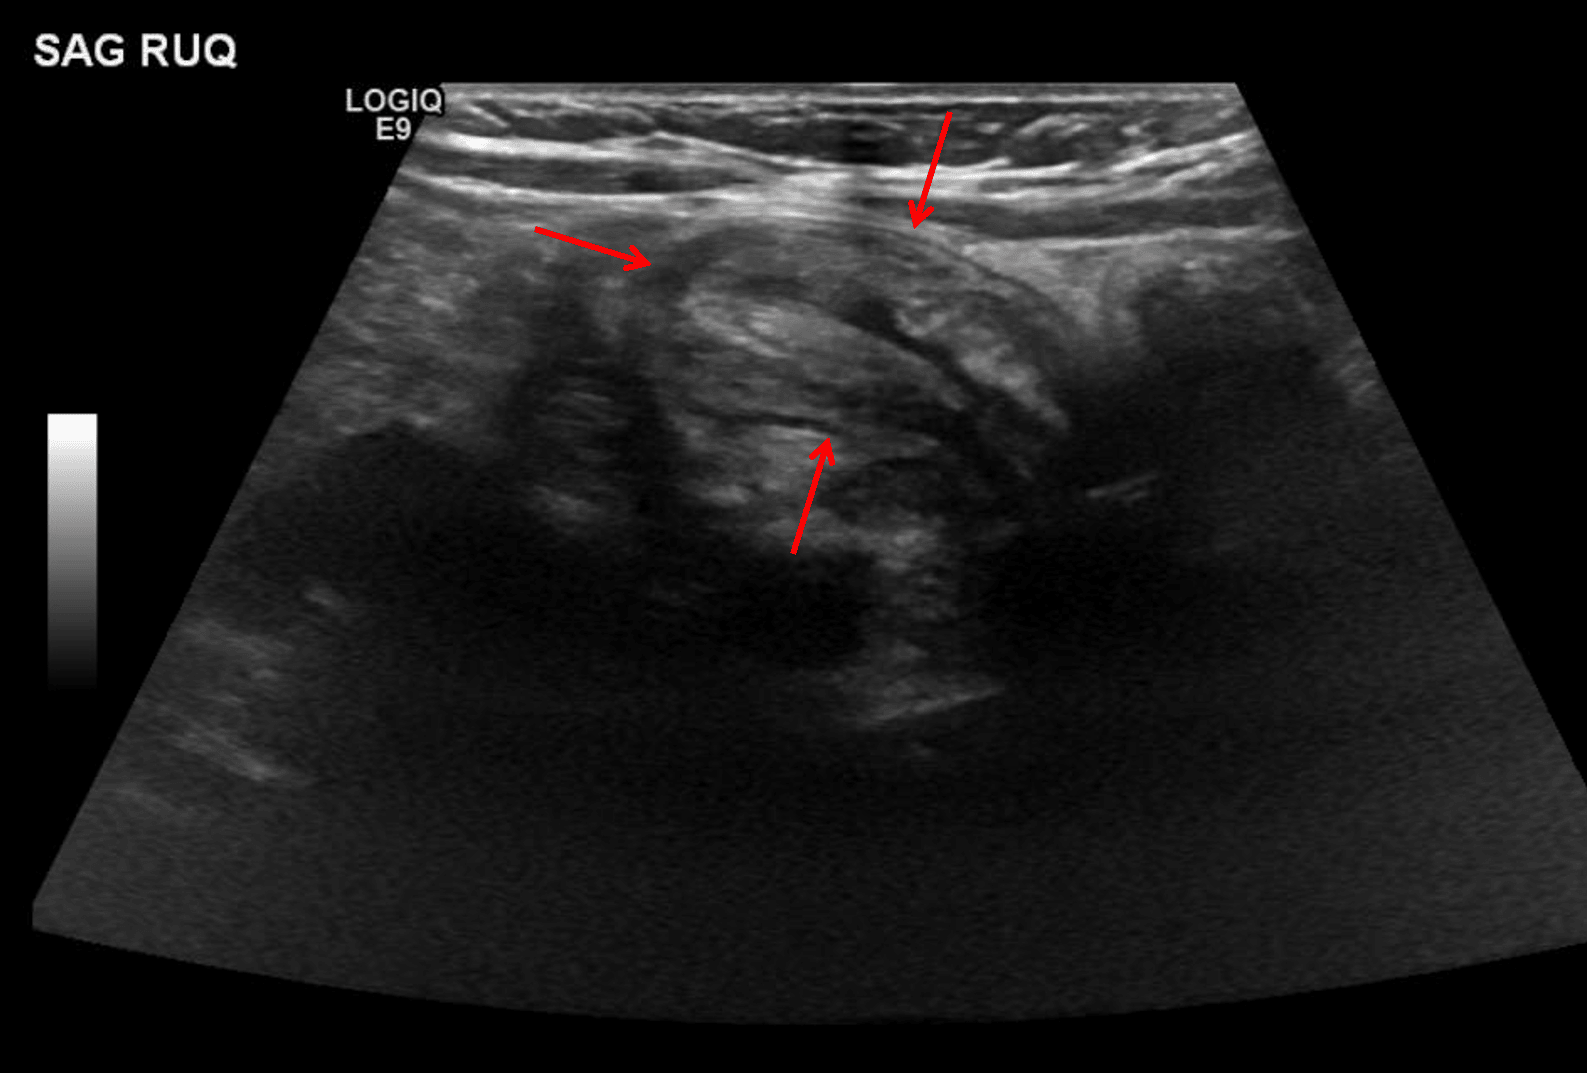

Findings

- Mass-like soft tissue density overlying the right upper quadrant

Diagnosis

Intussusception

Masslike soft tissue density overlying the right upper quadrant, which though nonspecific raises concern for intussusception. Recommend ultrasound for further evaluation.

- Radiographic signs of intussusception include:

- Soft tissue mass in the right hemiabdomen, which can have a targetoid appearance

- Distal small bowel obstruction

- Crescent of gas outlining the intussusceptum in the proximal colon

- While many of the radiographic findings of intussusception are nonspecific, it is important to alert the clinician to the possibility of intussusception when there is evidence of distal small bowel obstruction and/or a mass-like soft tissue density in the right hemiabdomen

Longitudinal view of an ileocolic intussusception in this patient (red arrows).